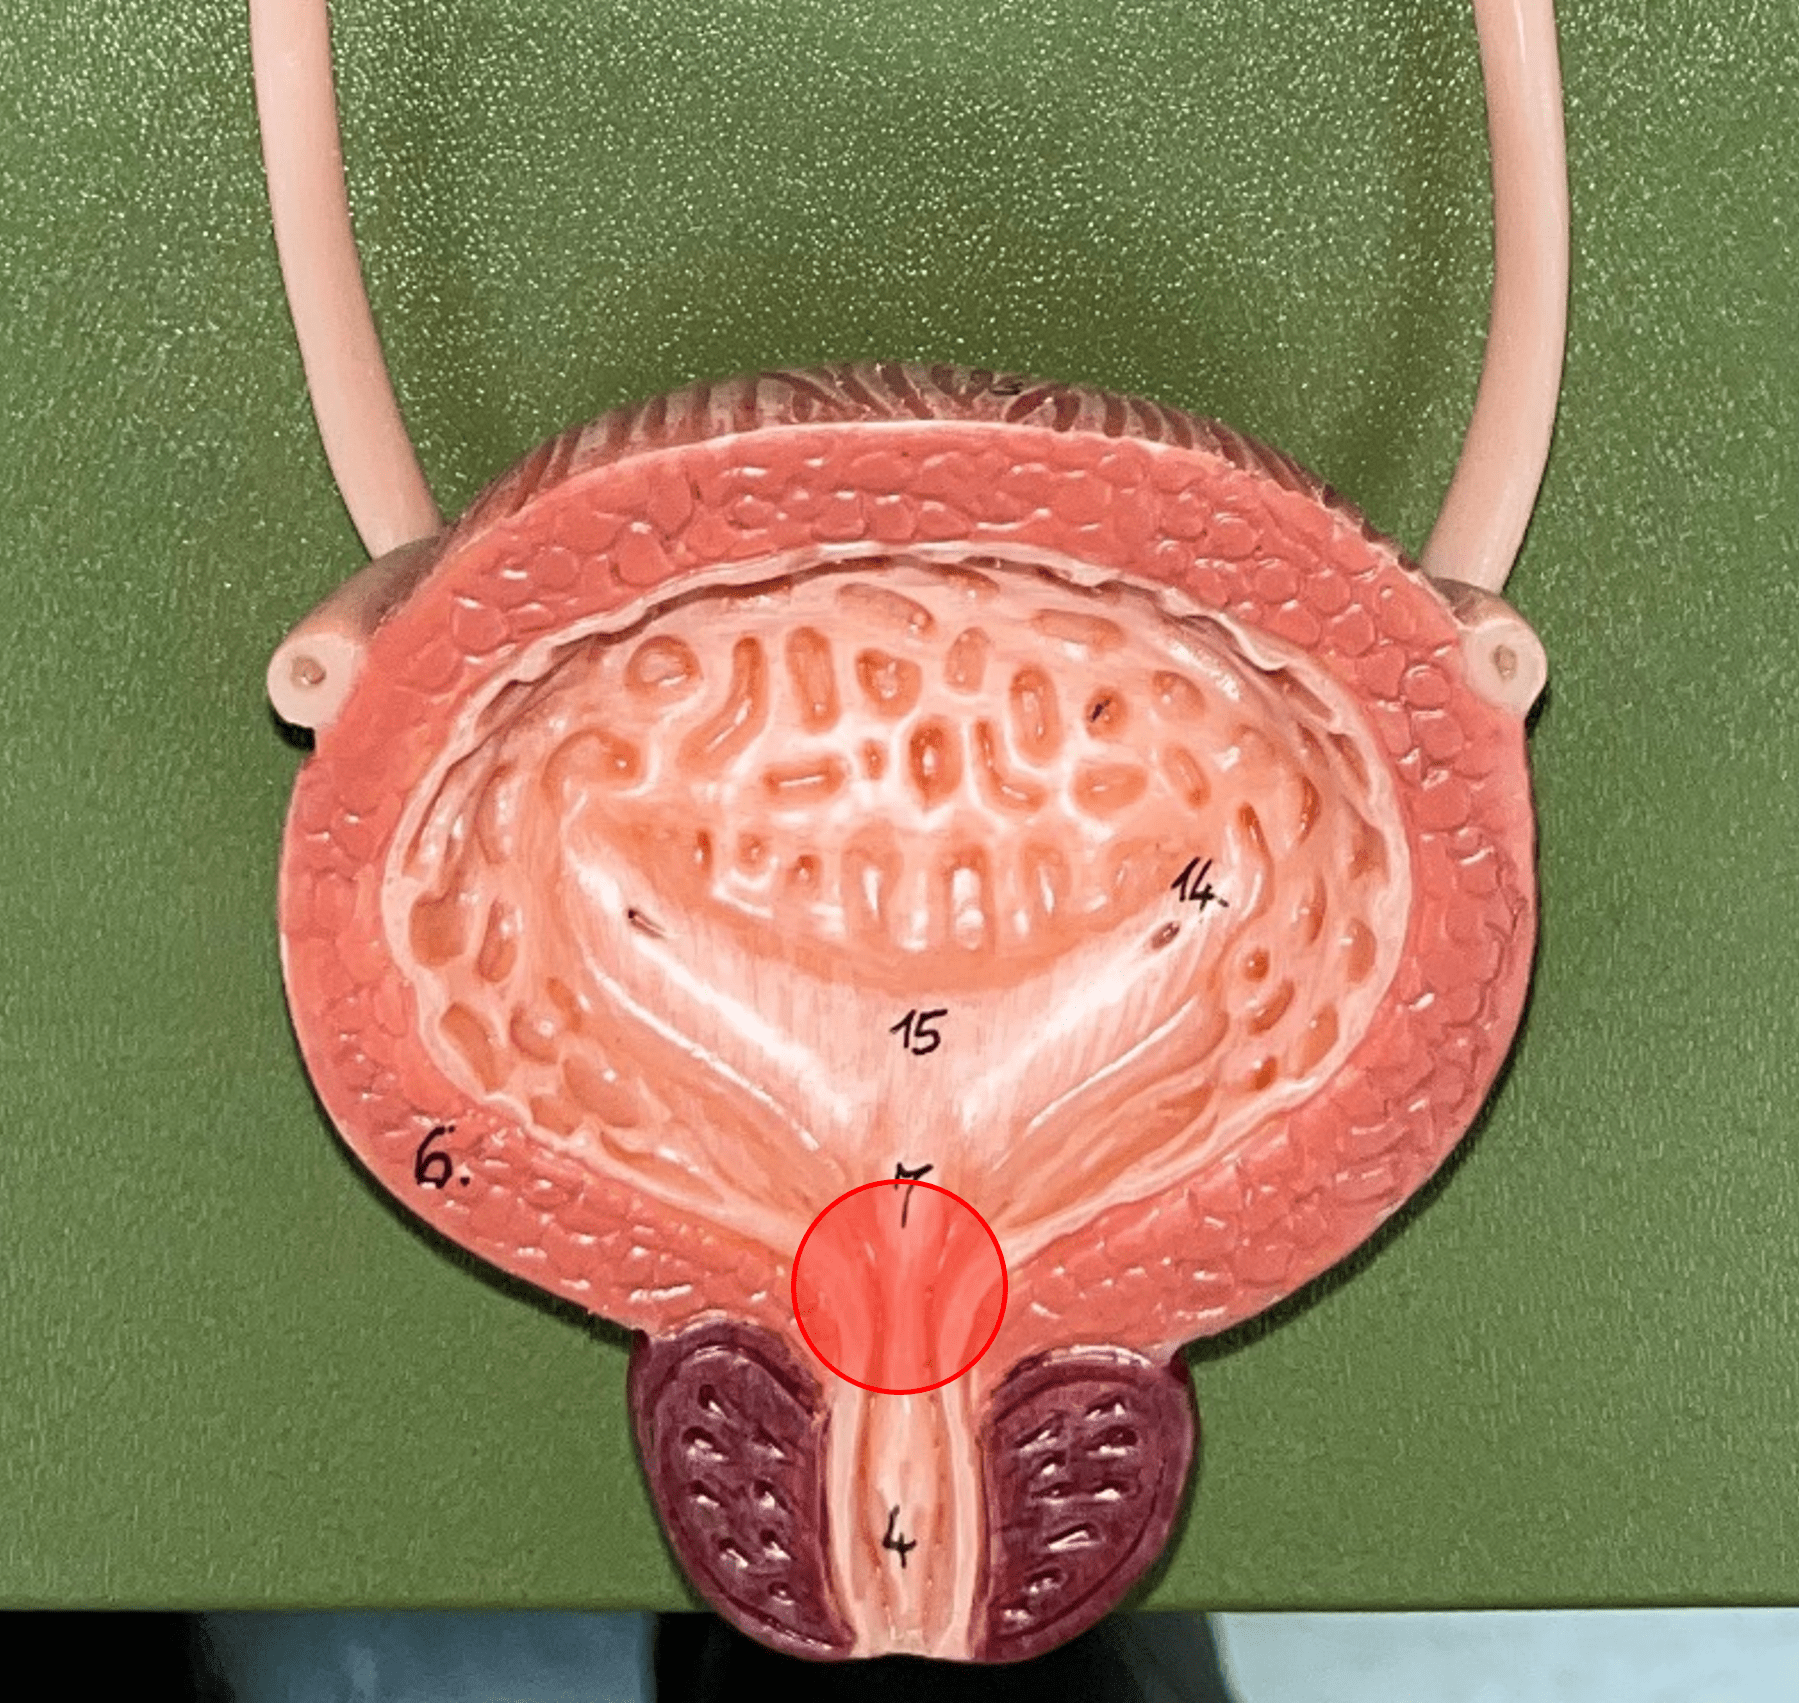

internal urethral orifice

• Part of the urinary bladder.

• The anterior opening of the bladder leading to the urethra.

• The anterior opening of the bladder leading to the urethra.